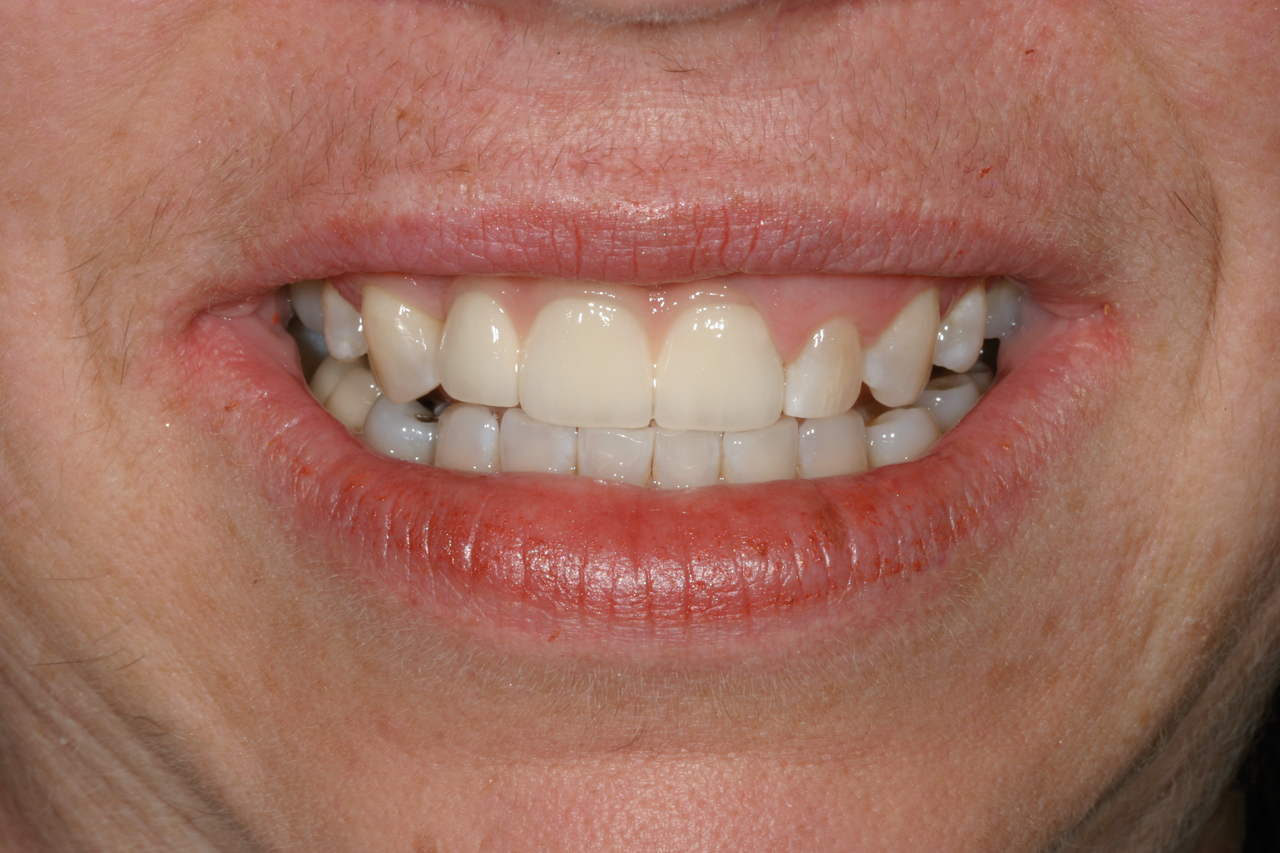

Fig 7. The gingival-colored porcelain was slightly visible upon smiling. This patient’s high smile line should have been the determining factor in the decision to restore or extract.

Figure 7